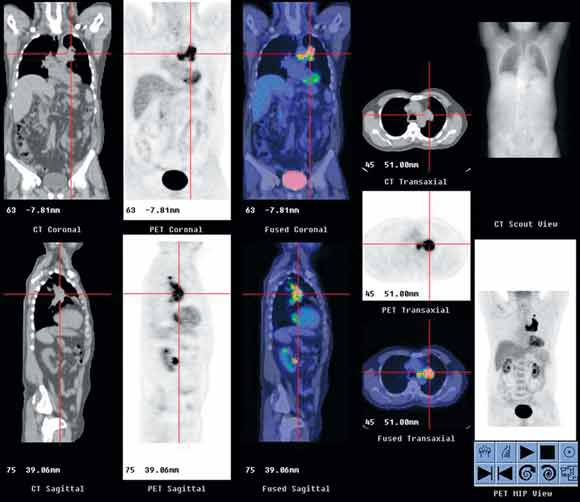

The resulting PET/CT studies are interpreted at a computer workstation with dedicated software allowing review of attenuation-corrected PET, CT and fusion PET/CT images in three orthogonal planes (Box 1). Both the CT and PET/CT fusion images are used to localise PET uptake abnormalities.

1 Typical positron emission tomography/computed tomography (PET/CT) workstation display

In this patient with cancer of the left lung, the display shows PET (black-and-white images), CT and PET/CT fusion (colour images) in three orthogonal planes, as well as CT scout image and whole-body PET images in AVI (audio-video-interleaved) format.